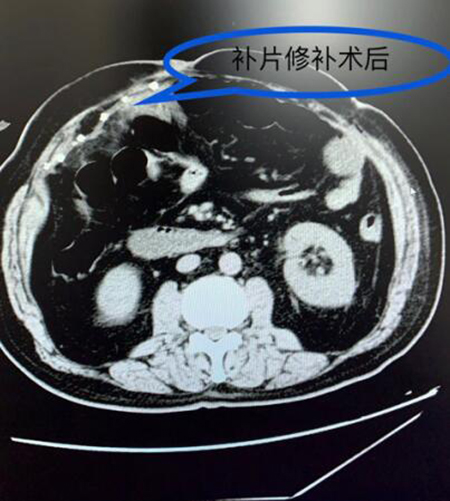

相比传统的开放手术需切开20公分的切口,腹腔镜手术只需要3个1公分的微创伤口,能达到大伤口开放手术达到的手术目的,而且可以减少伤口感染、补片感染的风险,术后恢复快、疼痛轻。但腹腔镜手术难度高,再加上何大爷10年前做过腹部手术,腹腔粘连重,腹腔镜下缝合腹壁缺损、放置补片技术要求很高。胃肠外科主任医师李菊芳与主治医师金杰波搭档,为何大爷实施了腹腔镜下巨大腹壁切口疝手术,手术圆满成功,患者顺利出院。

据悉,此例手术在何大爷之前医院没有开展此类手术记录,此类病人只有到上级医院去进行治疗。此例手术的成功,不仅是医院自主完成的首例,更体现着胃肠外科学科技术能力更上一层楼,已具备腹腔镜下处理复杂腹壁疝的能力,玉溪的病人不用上昆明,可以在家门口通过微创手术解决此类难题。(胃肠外科 金杰波)